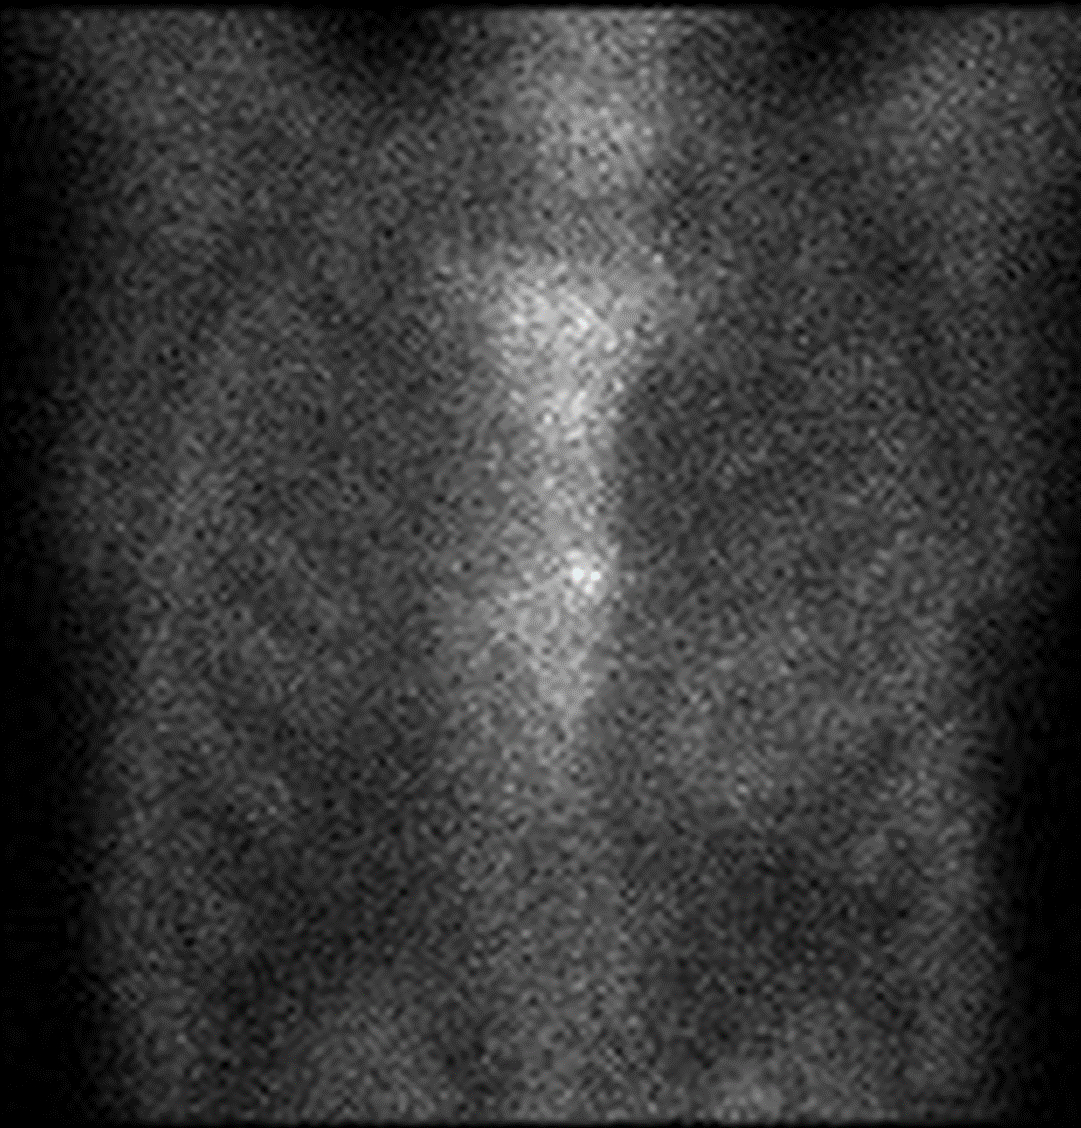

Abstract Body (Do not enter title and authors here): A Japanese male in his 80s was admitted to our emergency department with chest pain. His prior history was syncope and ventricular tachycardia. Transthoracic echocardiography (TTE) revealed thickening of the basal part of the antero-septal wall and thinning of the basal part of the inferior wall. Coronary angiography (CAG), cardiac MRI and blood test revealed no specific abnormalities. The day before his emergency admission, he visited the cardiology outpatient department for a periodic examination of cardiac hypertrophy. ECG, chest X-ray, and TTE were unchanged from his prior examination. However, that night, he experienced chest pain and was transferred to our hospital. On arrival, his vital signs were critical, with a blood pressure of 70/59 mmHg. ECG indicated ST elevation in antero-lateral leads. TTE detected pericardial effusion, and contrast-enhanced CT identified two focal areas of non-enhancement in the myocardium and pericardial effusion without signs of aortic dissection. CAG revealed no significant stenosis or obstructive lesion. During coronary angiography, the patient deteriorated to asystole. Cardiopulmonary resuscitation and percutaneous pericardial drainage were initiated. Hemorrhagic pericardial effusion was aspirated. Immediate surgical hemostasis was undergone, revealing about 2 cm lacerations and hematoma in the anterior and inferior wall. After surgery, he complained of abdominal discomfort. Esophageal gastrointestinal endoscopy was undergone to investigate the abdominal discomfort, and he was diagnosed with early gastric cancer. Endoscopic submucosal dissection (ESD) was undergone, and histopathological examination revealed adenocarcinoma and eosinophilic amorphous materials deposited in the submucosal vessels. Congo red staining of the submucosal vessels revealed orange-red areas. A technetium-99m pyrophosphatase scintigraphy showed Grade 2 uptake in the heart. Transthyretin (TTR) staining was positive in the specimen from ESD, leading to a diagnosis of TTR amyloidosis. Genetic test for TTR was negative, which led to a diagnosis of wild-type TTR amyloidosis and tafamidis was started. In cases of acute pericardial effusion and/or cardiac rupture, it is imperative to consider cardiac amyloidosis as a potential etiology, in addition to myocardial infarction and aortic dissection, especially in patients with left ventricular wall thickening, neuropathy, or abnormal ECG, also known as “red flag”.